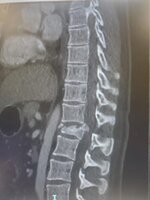

I broke my spine, had two surgeries (T12 arthrodesis), had to relearn how to walk again because I couldn't move my legs after the crash...